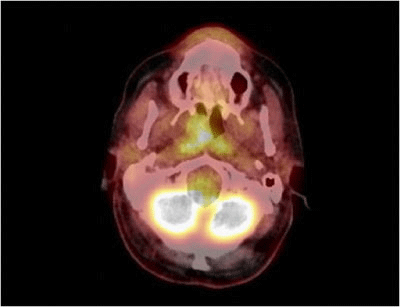

PET-CT showed only a metabolic uptake in the right nasopharynx with a Standard Uptake Value of 5.5 (Figure 3).

Figure 3 PET-CT scan showing only a metabolic uptake in the right nasopharynx due to Pleomorphic Adenoma.